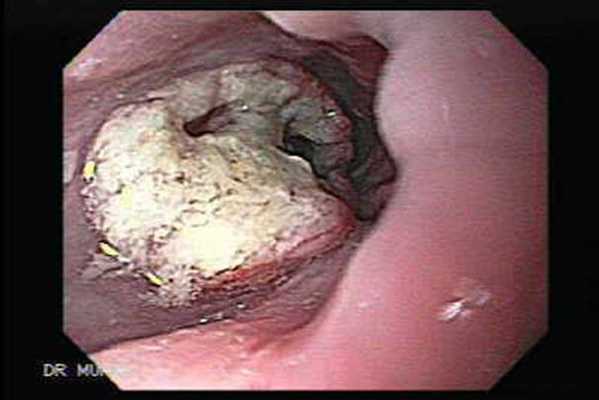

Второй основной метод исследования - эзофагоскопия, дающая возможность глазом увидеть в просвете пищевода опухоль или суженный участок, оценить распространенность и степень сужения.. Иногда только стойкость рентгенологической и эзофагоскопической картины позволяет отличить рак пищевода от его спазма, при котором самопроизвольно или после введения антиспастических средств сужение исчезает и восстанавливаются нормальные просвет и проходимость пищевода. Завершающий этап диагностики - биопсия под контролем эзофагоскопа для гистологического или цитологического исследования.

Эндоскопическая картина аденокарциномы

Эндоскопическая картина плоскоклеточного рака